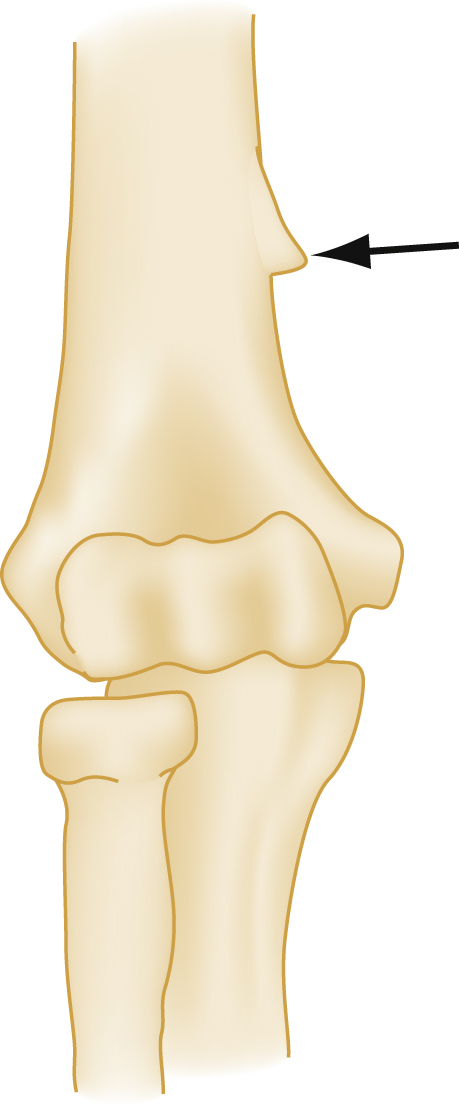

Supracondylar process of the humerus (arrow) is present in approximately 2.5% of cases just proximal to the medial epicondyle. Volar surface of right elbow is shown.